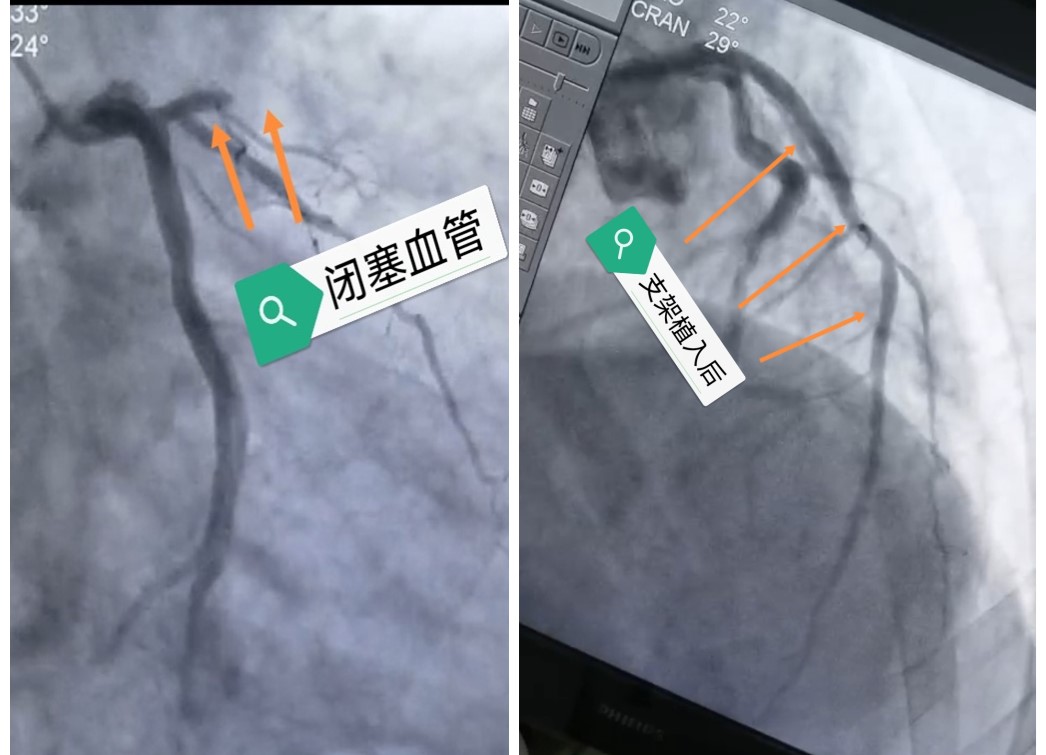

为了缩短救治时间,荆佳平医生会诊后建议对该病人进行双绕直达导管室,但由于患者无家属陪同,故沟通未果。经药物溶栓后患者症状得到缓解,顺利到达我院胸痛中心,在我院急诊内科值班医生白岩松和胸痛中心值班医生荆佳平诊查后,一致考虑患者病情十分危重,随时有猝死的危险,立即开通了胸痛救治绿色通道,荆佳平医生当机立断电话联系患者家属交代病情及沟通治疗方案,经家属同意后,患者在未收取任何费用的情况下立即送至导管室,由心内二科赵贵明主任、荆佳平医生及崔迎辉医生行急诊冠状动脉造影术,造影提示患者心脏的冠状动脉血管中最重要的一支前降支近段严重闭塞,立即进行开通血管治疗,患者术中突现意识不清、抽搐,心电监护显示室颤,给予电除颤及心肺复苏,同时,静脉推注盐酸胺碘酮,共除颤五次,患者意识终于恢复,恢复窦性心律,手术得以继续。于前降支植入3枚药物支架后,血流完美恢复,随即胸痛消失,术后患者送至CCU继续恢复治疗。目前患者状态良好,生命体征平稳。次日赶到的家属心怀感激感慨道:“是通辽市胸痛联盟急救体系救了我们的命啊!”